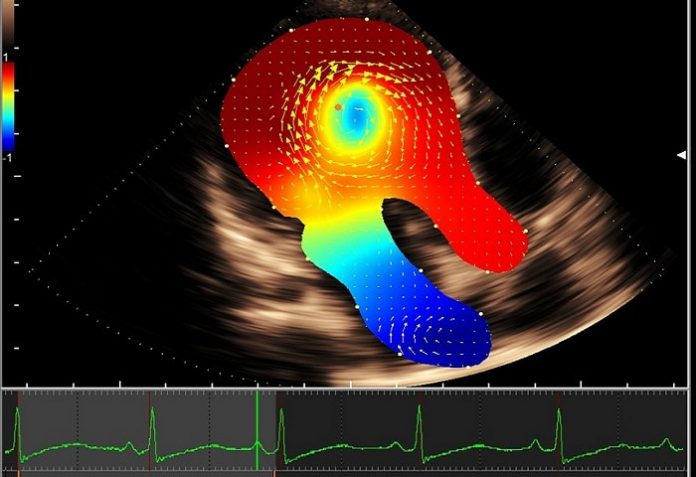

Hitachi Medical Systems Europe introduced what it calls the next level of intelligent Vector Flow Mapping (iVFM) at EuroEcho Imaging 2018, Dec. 5-8 in Milan, Italy.

The third generation of Hitachiβs non-invasive intracardiac blood flow visualization technology provides unique information about the intraventricular vortex and its energetic efficiency, including kinetic energy loss, relative pressure, or wall shear stress display and analysis.

Built on the premium 2-D/4-D/4G CMUT Lisendo 880LE ultrasound system as part of the HDAnalytics CV analysis package, the new iVFM features faster data processing through automation for a simplified workflow. The embedded iVFM is now available for both intracardiac and vascular flow structures.